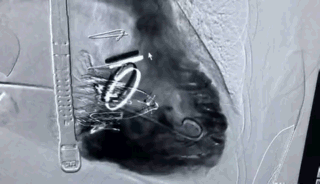

瓣膜植入后右心室造影